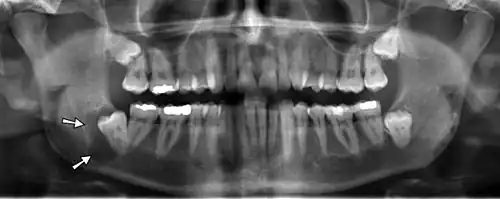

Panoramic radiographs have the capability to demonstrate a portion of the neck and display atheromas (calcifications in the carotid artery) which are an indication of both local and generalized (systemic) atherosclerosis. Atherosclerosis of the coronary arteries leading to myocardial infarction (heart attack), and atherosclerosis of the carotid artery leading to stroke are the number one and number three most common causes of death in the United States.[6]

There is interest to look at panoramic radiographs as a screening tool, however further data is needed with regards if it is able to make a meaningful difference in outcomes.[7]

Epidemiology: general public and high risk groups

Additional research projects have further determined the prevalence rate of these atheromas in the general population (3–5%)[8][9] and among high-risk groups (over 25% in: recent stroke victims,[10] individuals with obstructive sleep apnea syndrome,[11][12][13] postmenopausal women,[14] type 2 diabetics,[15][13][16] individuals with dilated cardiomyopathy,[17][13] and among individuals who have received radiotherapy directed at the neck,[18][19]). These findings have been corroborated by other several other researchers.[20][21][22][23][13]

Atherosclerosis is attributed to risk factors that include cigarette smoking, hyperlipidemia, obesity, diabetes mellitus, and hypertension (high blood pressure). These factors, however, do not fully account for the risk of disease. Atherosclerosis has been conceptualized as a chronic inflammatory response to endothelial cell injury[24] and dysfunction possibly arising from chronic dental infection. In 2010, using the previously validated Mattila panoramic radiographic index to quantify the totality of dental infection (i.e., periapical and furcal lesions, pericoronitis sites, carious tooth roots, teeth with pulpal caries, and vertical bony defects), Friedlander's group determined that individuals with carotid artery atheromas on their panoramic radiographs had significantly greater amounts of dental infection/inflammation than atherogenic risk-matched controls devoid of radiographic atheromas.[25][26] While the Mattila index had been previously used to relate the extent of dental infection to coronary artery disease, this research is the first to link the full range of dental disease that it measures to panoramic radiographs evidencing calcified carotid artery atherosclerosis.